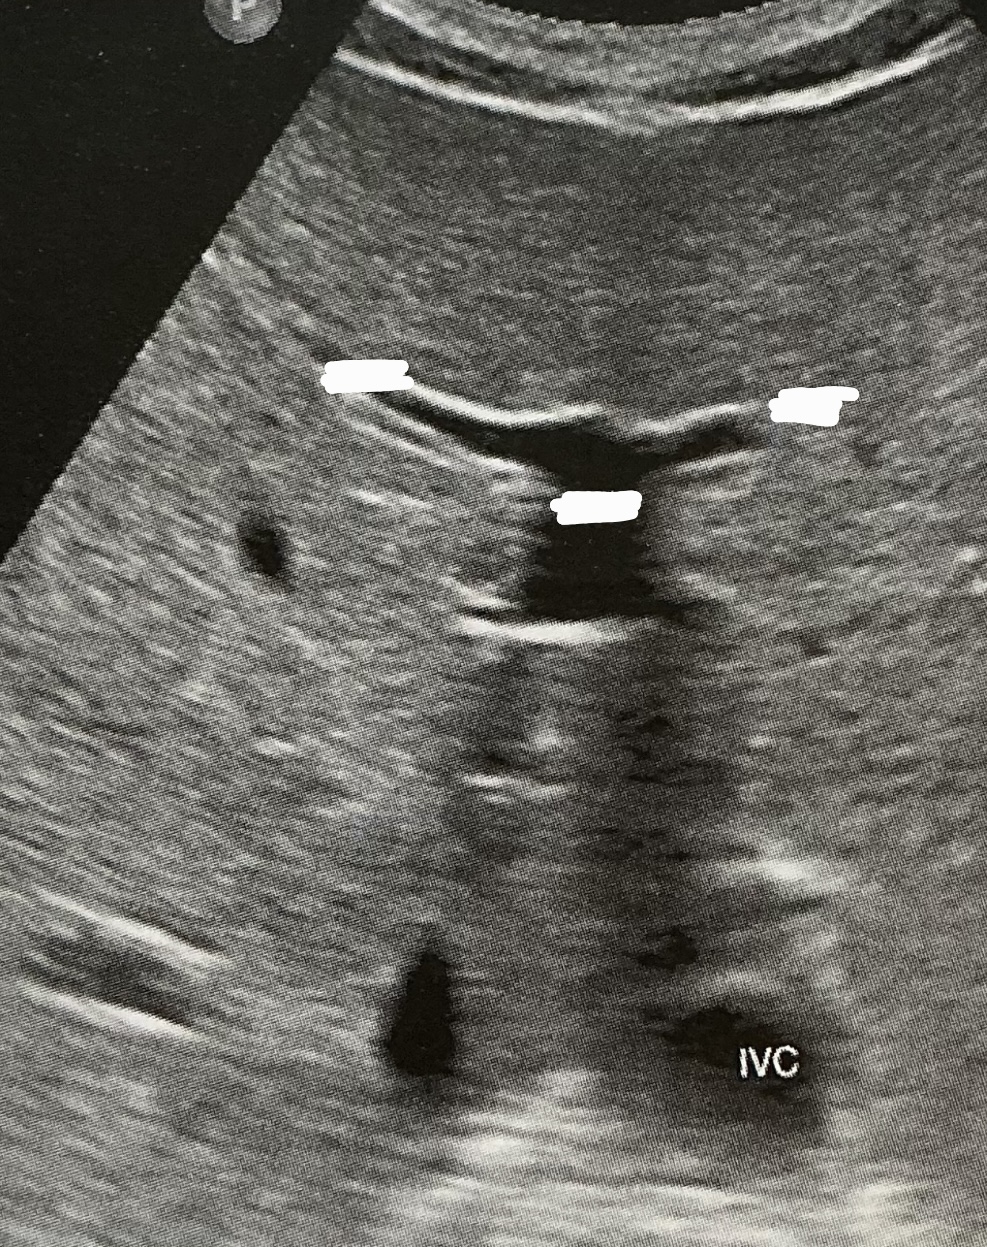

Label this picture

what sign is it depicting

Why does this happen?

What sign does the hepatic veins normally depict?

Canadian moose sign

Dilatation from right heart failure

Playboy bunny sign